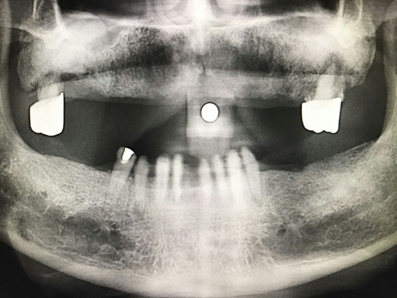

毛國斌種植病例——群討論分享